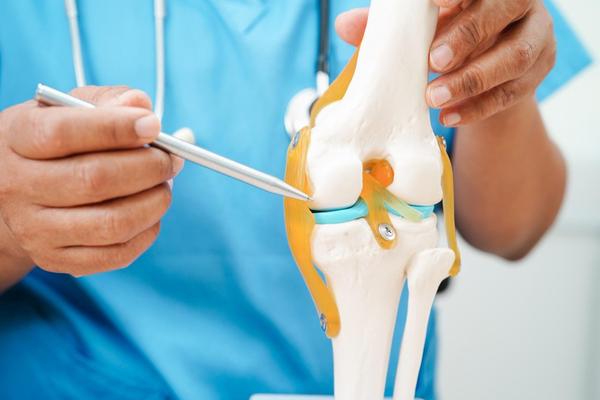

Partial Knee Replacement Surgery

Partial Knee Replacement Surgery At Anand Ortho Care Centre – Rohini, Delhi By Dr. Ritesh Dang – Senior Orthopaedic & Joint Replacement Surgeon If you're suffering from localized knee pain due to arthritis or injury, but your entire knee joint isn’t damaged, Partial Knee Replacement could be the ideal solution. At Anand Ortho Care Centre, we offer advanced Partial Knee Replacement – a minimally invasive procedure that replaces only the damaged part of your knee, preserving healthy bone and tissue for a faster, more natural recovery. ✅ Benefits of Partial Knee Replacement Less Invasive: Smaller incision and less bone removal Faster Recovery: Shorter hospital stay and quicker return to daily activities More Natural Movement: Preserves healthy bone, cartilage, and ligaments Reduced Pain & Better Mobility: Specifically targets damaged area for lasting relief Ideal for Younger or Active Patients 👨‍⚕️ Why Choose Dr. Ritesh Dang? With years of specialized experience in knee preservation and replacement, Dr. Ritesh Dang is known for his patient-first approach and surgical precision. He helps patients regain mobility with the latest techniques, including robot-assisted partial knee replacement for improved accuracy and longevity of the implant. 📍 Clinic Address: Anand Ortho Care Centre B-39, Prashant Vihar Road, Opposite to CRPF School, Prashant Vihar, Sector 14, Rohini, Delhi – 110085 📞 Contact: 08048035351 🗺️ Get Directions on Map 🕒 Clinic Timings: Open Today: 6:30 PM – 8:30 PM Monday to Saturday: 6:30 PM – 8:30 PM (Sunday Closed) 📅 Schedule Your Consultation Today Don’t let knee pain slow you down. Find out if Partial Knee Replacement is right for you. Call Now: 08048035351 Walk-in consultations available during clinic hours.